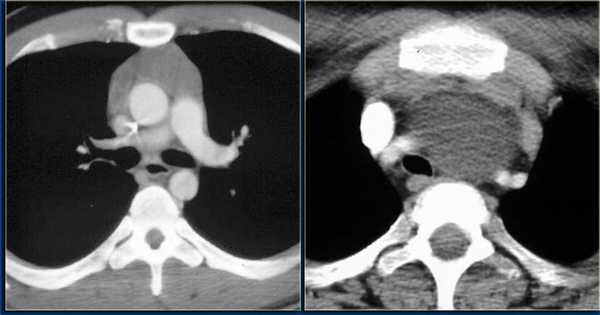

Компьютерная томография с контрастированием — более информативный метод. Он позволяет получить информацию о наличии новообразования, определить его злокачественность, и даже дифференцировать его природу — отличить тимому от лимфомы и др. МРТ не является рутинным методом диагностики тимом, но может использоваться по показаниям, например, при наличии у пациента аллергии на йодсодержащий контраст, применяемый при КТ.

При проведении компьютерной томографии оценивают наличие вилочковой железы и положение в средостении: уровень и отношение к срединной линии, ее форму, линейные размеры, однородность структуры, четкость контуров, измеряют плотность нативно, а также в артериальную, венозную и отсроченную стадии. Аксиальные изображения КТ и комбинированные мультиплоскостные реконструкции могут быть использованы, чтобы идентифицировать инвазию опухоли в крупные кровеносные сосуды, перикард и легочную ткань. Если, опухоль имеет гладкие, четкие границы, однородную плотность, отсутствуют некрозы или кистозные изменения, видна жировая прослойка между опухолью и смежными структурами новообразование можно считать неинвазивным. Если, опухолевое новообразование имеет дольчатую или неправильную форму, нечеткие контуры, неоднородное усиление после внутривенного контрастирования, явное прорастание перикарда, легочной ткани, грудной стенки такую опухоль необходимо считать инвазивной.

На рентгенограмме грудной клетки тимома имеет вид объемного образования неправильной формы, расположенного в переднем средостении. КТ грудной клетки значительно расширяет объем информации, полученный при первичной рентгендиагностике и в ряде случаев позволяет поставить морфологический диагноз. Уточнение локализации и взаимоотношения новообразования с соседними органами при КТ средостения позволяет в дальнейшем выполнить трансторакальную пункцию опухоли средостения, что чрезвычайно важно для гистологического подтверждения диагноза и верификации гистологического типа тимомы.